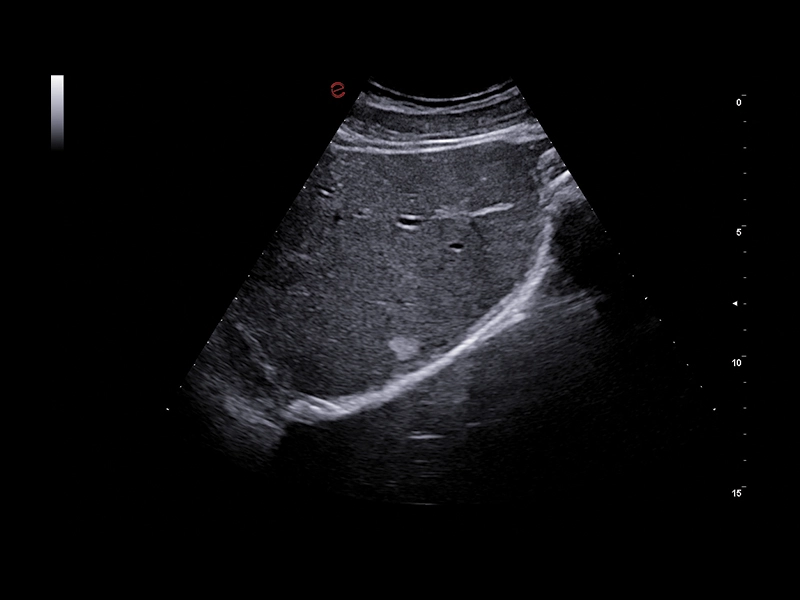

MyLab™X9 - Liver 01

MyLab™X9 - Liver 01

MyLab™X9 - Liver 02

MyLab™X9 - Liver 02

MyLab™X9 - Liver 03

MyLab™X9 - Liver 03

MyLab™X9 - Liver 04

MyLab™X9 - Liver 04

MyLab™X9 - Liver 05

MyLab™X9 - Liver 05